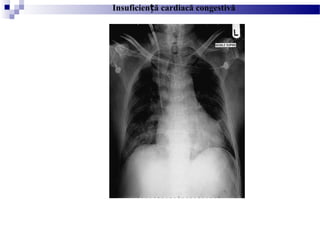

INSUFICIEN A CARDIACĂ CONGESTIVĂȚ

- Este una dintre cele mai comune anomalii evaluate pe

radiografia toracica

- Apare atunci când cordul nu reu e te să men ină un debitș ș ț

adecvat

- Poate progresa către hipertensiune venoasă pulmonară iș

edem pulmonar cu scurgere de fluid în intersi iu, alveole sauț

spa iul pleuralț

- Primul semn care apare pe radiografia toracică este

cardiomegalia, definită ca cre terea indexului cardio-toracicș

(>0,5).

- În vascularizatia pulmonara a unui torace normal, venele

pulmonare inferioare sunt mai mari decat cele superioare datorită

gravită ii; la un pacient cu insuficien a cardiacă congestivă,ț ț

presiunea capilară pulmonară cre te până la valori de 12-ș

18mmHG, iar venele din partea superioară se dilată fiind egale

sau mai mari in dimensiune, termen denumit cefalizare.

- Prin cre terea presiunii pulmonare (18-24mmHg) apareș

edemul intersti ial i liniile Kerleyț ș

- Cre terea peste acest nivel a presiunii capilare pulmonareș

corespunde edemului alveolar, adesea sub aspectul clasic de

”aripi de liliac”

- Revărsatul pleural este deasemenea des întâlnit

- Radiografia toracica este importanta in evaluarea pacientilor

cu insuficien ă cardiacă congestiva pentru a urmări evolu iaț ț

edemului pulmonar i a evalua răspunsul la tratament.ș

- cardiomegalie, edem alveolar, margini vasculare

slab definite

Insuficien ă cardiacăț

congestivă severă

Insuficien ă cardiacă congestivăț